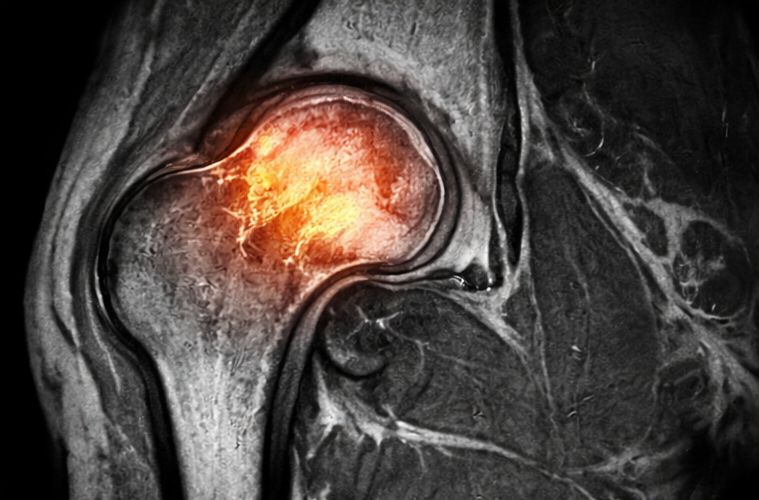

Avascular necrosis (AVN) of the head of femur is a progressive orthopedic condition characterized by compromised blood supply to the femoral head, leading to bone ischemia, structural collapse, and secondary osteoarthritis if untreated. It commonly affects young and middle-aged adults and is associated with risk factors such as corticosteroid use, alcohol abuse, trauma, and certain systemic diseases. Clinical presentation ranges from asymptomatic early disease to severe hip pain and functional limitation in advanced stages. Diagnosis relies on clinical suspicion supported by imaging, with magnetic resonance imaging (MRI) being the gold standard for early detection. Management strategies depend on disease stage and include conservative measures, pharmacologic therapy, joint-preserving surgical procedures, and total hip arthroplasty in advanced cases. This case report describes a young patient with avascular necrosis of the femoral head, highlighting clinical features, diagnostic evaluation, management, and short-term outcomes. Early diagnosis and timely intervention are essential to delay disease progression and preserve joint function.

MRI is the most sensitive modality for early diagnosis, allowing detection before radiographic changes become evident. Early-stage disease can be managed with conservative and joint-preserving surgical techniques such as core decompression, which aims to restore blood flow and delay disease progression. Advanced stages often require total hip arthroplasty, which is less desirable in young patients due to implant longevity concerns.